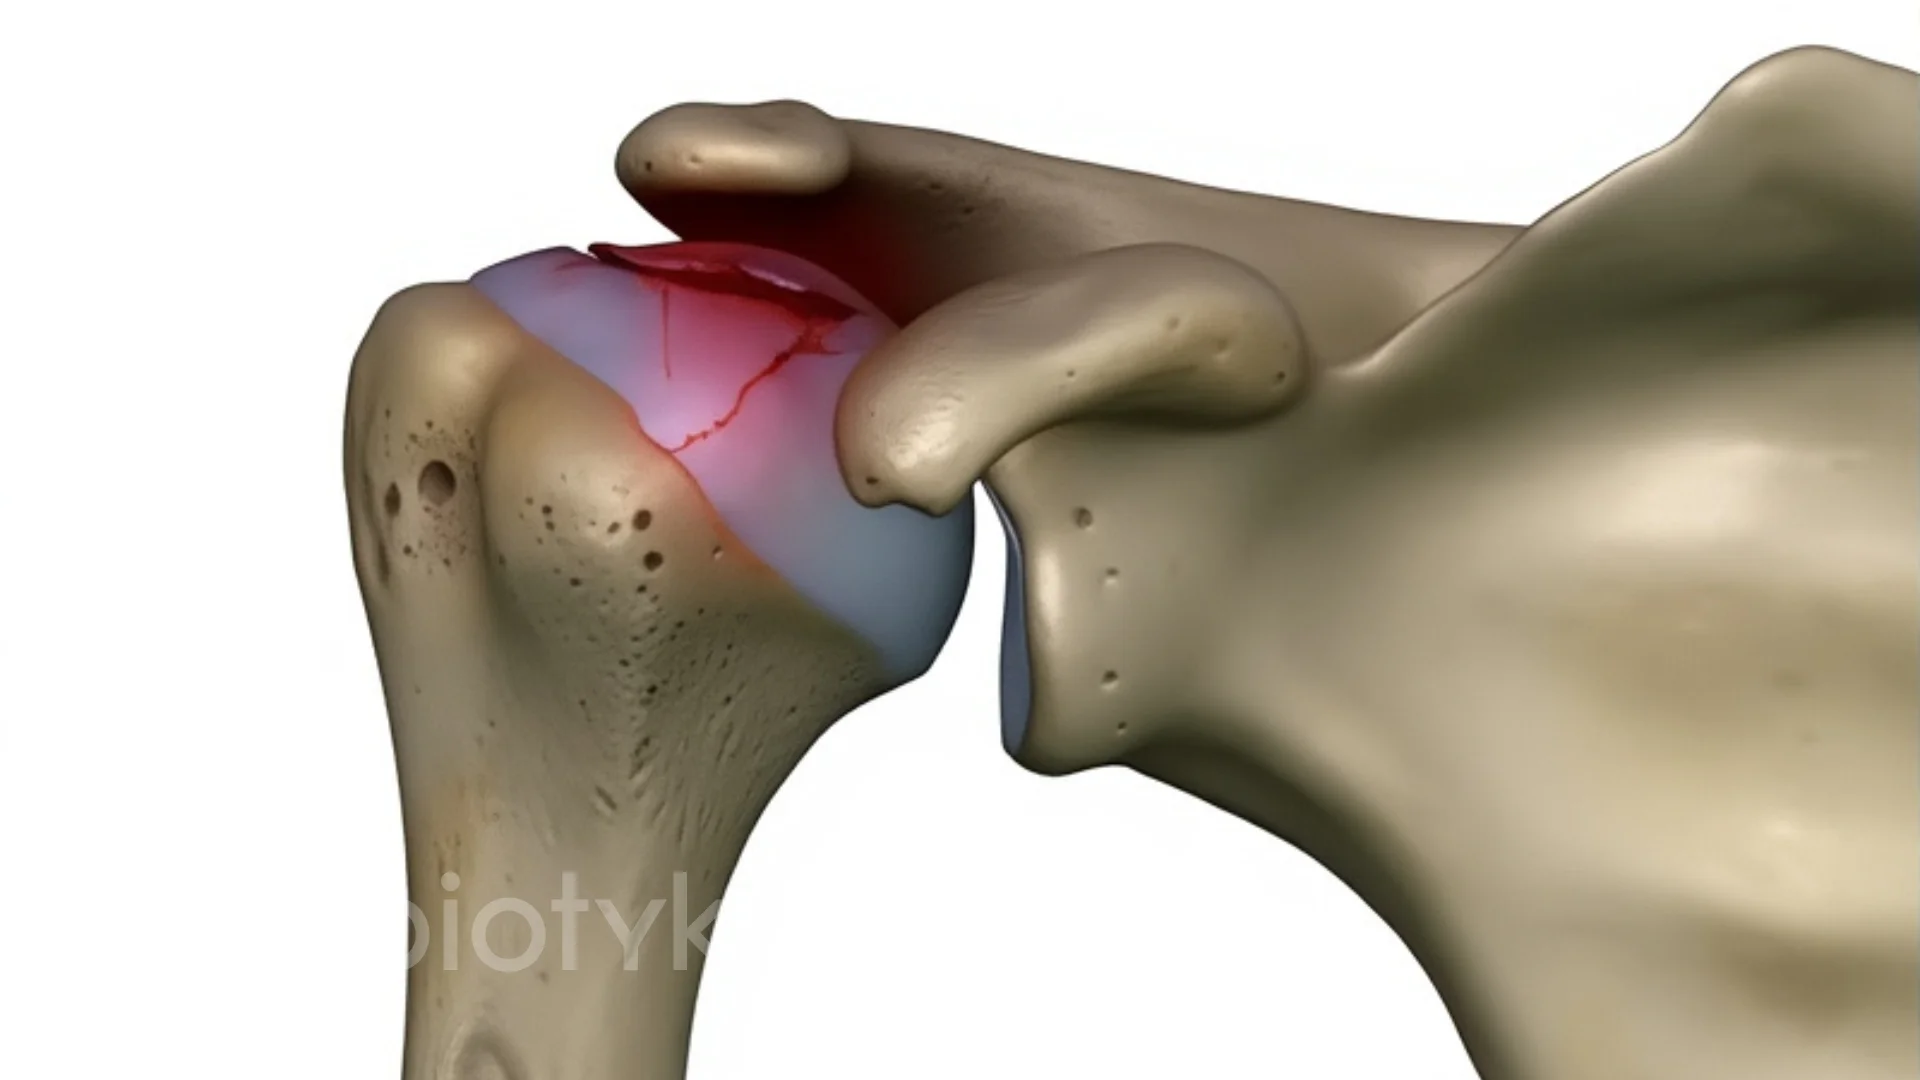

Зношена голівка плечової кістки та уражені ділянки суглобової западини лопатки обережно видаляються. При потребі проводиться корекція навколишніх тканин.

У плечовій кістці формується канал для встановлення ніжки імпланта. Поверхня западини лопатки обробляється для точного розташування штучної «чаші».